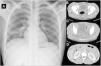

Se le realiza una radiografía de tórax (fig. 1A) que revela una elevación del hemitórax derecho y un leve infiltrado homolateral. En la tomografía computarizada abdominal (fig. 1B, C y D) muestra imágenes que indican una tuberculosis abdominal, junto a colecciones de hasta 14cm en región presacra con extensión a glúteo mediano con múltiples áreas de osteomielitis. En las muestras del lavado broncoalveolar y del drenaje del absceso glúteo, los cultivos fueron negativos, incluyendo el Lowenstein. Sin embargo, la reacción en cadena de la polimerasa para Mycobacterium tuberculosis resultó positiva. Además, los cultivos de esputo y de orina para micobacterias resultaron negativos. Se inicia tratamiento tuberculostático. El paciente presenta buena respuesta, aunque experimenta un episodio autolimitado de hematuria. Se solicita un estudio parasitológico en orina. En el estudio microscópico del sedimento urinario, se observan numerosos huevos largos y ovalados (110-170μm de largo por 40-70μm de ancho) con un espolón terminal (fig. 2), portando en su interior una larva miracidio. Los huevos eclosionados liberaron la larva miracidio móvil, pudiendo apreciarse las principales estructuras como la papila apical y los cilios (vídeo).

A: radiografía de tórax y donde se observa la elevación del hemitórax derecho y un leve infiltrado en hemitórax derecho. B, C y D: Tomografía computarizada abdominal que muestra hallazgos radiológicos sugerentes de tuberculosis abdominal (múltiples adenopatías, engrosamiento peritoneal, líquido libre). Gran absceso lobulado de hasta 14cm en región presacra con extensión a glúteo mediano. Áreas de osteomielitis.